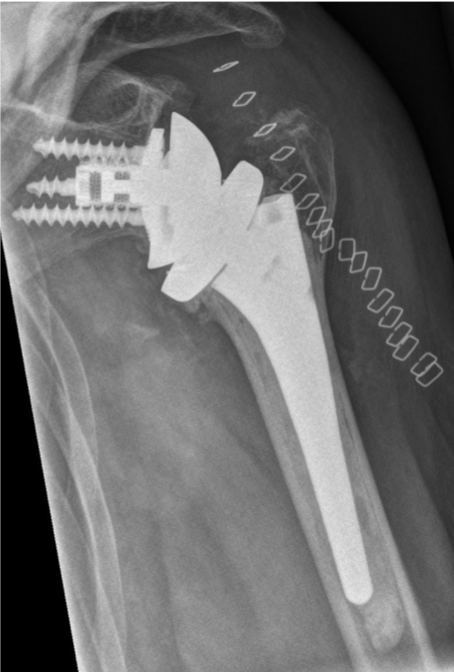

Post-op

Implantation of the LINK Embrace

- Cemented Humeral Standard Stem

- Reverse Glenoid Baseplate with the TrabecuLink structure for bone integration with central and peripheral screws

- Neutral glenosphere 39 mm diameter with good inferior overhang

Result:

- Excellent primary stability

- Good ROM

- Good pain relief

- Optimal soft tissue tension due to selection of appropriate components (neutral glenosphere, reverse insert height 0)